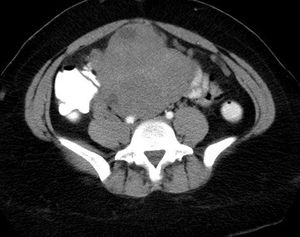

Endometrial Stromal SarcomaBySushila Ladumor, MDMay 31st 2011Endometrial stromal sarcoma (ESS) is a rare malignant tumor of the endometrium, occurring in the age group of 40-50 years.